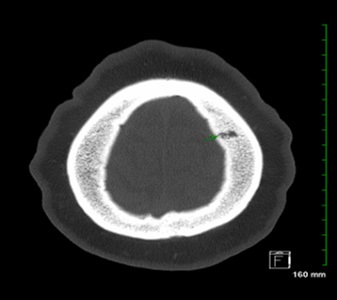

A few months later she presented to the ED again for worsening solid food dysphagia and headaches. Repeat PET scan showed a new FDG avid GE-Junction mass with persistent lymphadenopathy. A diagnostic EGD was performed, revealing distal esophageal (figure 2) and gastric ulcers. Biopsies came back positive for HSV (figure 3) and candida; and treatment with acyclovir and fluconazole was initiated.

Figure 2: